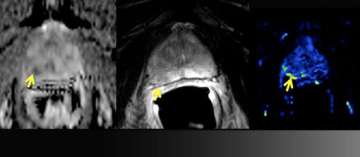

7) MR-Guided Targeted Biopsy

- 63 y/o, PSA 8.8 → 13.2 over 5 years

- All systematic biopsies negative

- Hypointense left anterior lesion with restricted diffusion is moderately suspicious, not in biopsy zone